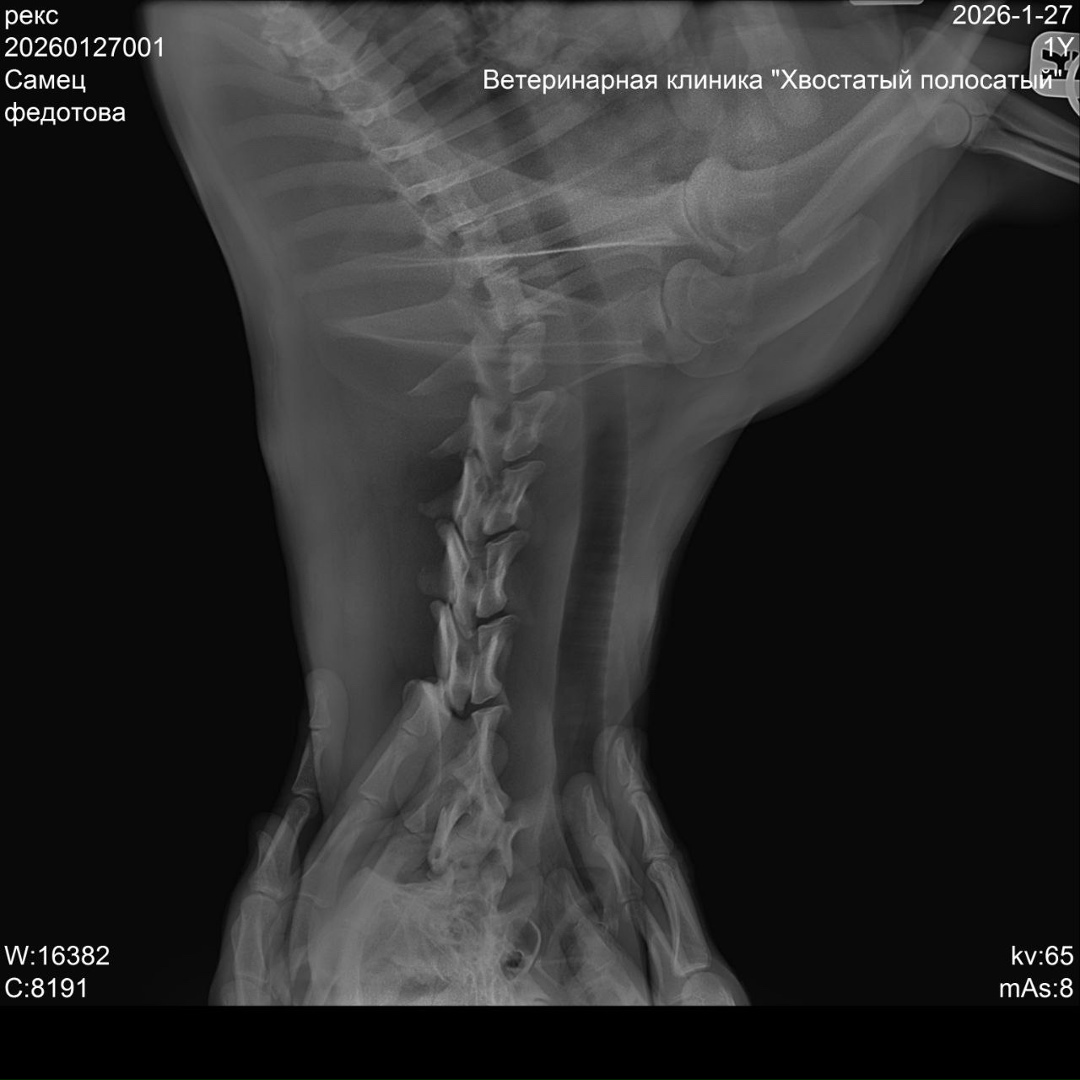

Срочный ‼️ пост сбор!!!!!!! Умоляем помогите!!!!!!Друзья,у нас экстренный сбор!Все кто следит за моей страницей,думаю помнят летом с Абхазии я привезла кошку с опухолью ,котенка и двух щенков,спасибо приюту «Умка»они приняли тогда у меня щенят,вылечили и пристроили в семьи,но сегодня случилась беда Тима(теперь он Рекс)сбила машина у дома,хозяева нашли его утром ,взяли такси и приехали в Пермь с Кукуштана,у Рекса перелом лапы и позвоночника,и черепно мозговая травма,сегодня его оставили на стационаре капать и обезболивать.Нужна операция,которая многодетной семье не по карману.Нас согласились прооперировать в клиникеДойчевет сумма 80000 тыс,я не знаю соберем ли мы такие деньги,но не оставлять же его инвалидом.Сбор буду вести на свою карту,отчитаюсь под постом!Карта Сбербанка 2202206854425829 привязана к моему номеру телефона 89922395800 Лукиных Елена Валентиновна. Пометка Рексу.Спасибо всем кто нас не бросает,прошу помощи в репостах.